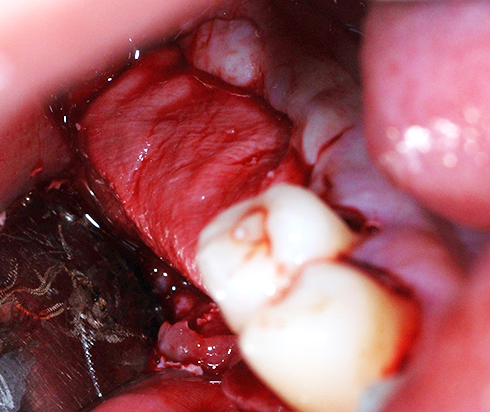

Another clinical case using non resorbable membrane and bone tac

• Another clinical case using  non resorbable membrane and bone tac 1